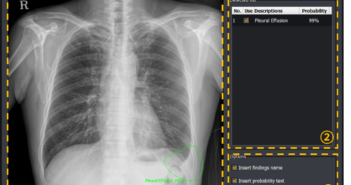

뷰웍스는 기업 부설연구소에서 자체 개발한 인공지능 기반 흉부 진단보조 솔루션 ‘VXCAD-CXR’에 대해 식품의약품안전처 인증을 취득했다고 20일 밝혔다. ‘VXCAD-CXR’은 흉부 방사선 촬영 영상을 분석해 질환이 발생했을 것으로 의심되는 부위와 병증 확률(abnormality)을 자동으로 제시하는 인공지능 기반의 진단보조 솔루션이다. 주요 흉부 질환인 ▲흉수(Pleural Effusion) ▲기흉(Pneumothorax) ▲결절 및 종괴(Nodule and Mass) 3종의 질환에 대한 발병 확률과 병변 부위에 대한 정보를 제공, 현장에서 의료진이 곧바로 소견을 제공받을 수 있게 된다. ‘VXCAD-CXR’의 인허가 취득 배경에는 국내 관계기관의 적극적인 협업이 있었다. 먼저 개발 과정에서는 산업통상자원부와 한국산업기술시험원(KTL)이 주관하는 ‘영상진단 의료기기 탑재용 AI기반 영상분석 솔루션 개발사업’의 일환으로 제공된 영상 데이터셋을 활용했다. 뷰웍스 김후식 대표이사는 “응급 의료 서비스 수요 증가와 고도화되는 헬스케어 시장 상황에 맞춰 의료기기 기업의 인공지능 기반 진단보조 솔루션 개발은 선택이 아닌 필수가 되고 있다”며 “뷰웍스에 내재된 인하우스(In-house) 개발 역량을 동력원으로 삼아 높은 부가가치를 창출하고, 의료영상 솔루션 혁신을 이어갈 것”이라고 전했다.